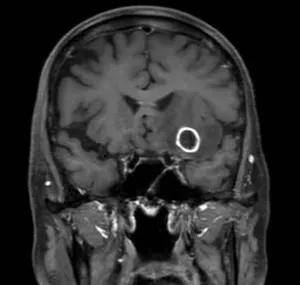

頭部造影MRI検査画像 頭部造影MRI検査画像 頭部造影MRI検査画像

頭部造影MRI検査画像(肺がん脳転移)